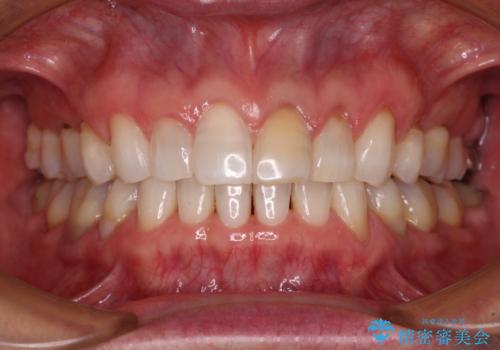

- 1年10ヶ月

- 前歯の開咬を気にして来院された患者様です。

開咬の治療は、前歯を閉じるように動かすとともに、上下臼歯を圧下(骨内にめり込ませる)させることで進めて行きます。

インビザラインは臼歯の圧下を効果的に行えるため、インビザラインを用いて矯正治療を行うこととしました。

オープンバイトは舌の突出癖により誘発され、治療後も突出癖が残っている容易に後戻りしてしまいます。

治療期間を短縮するためにも、舌突出癖の改善が極めて重要となります。